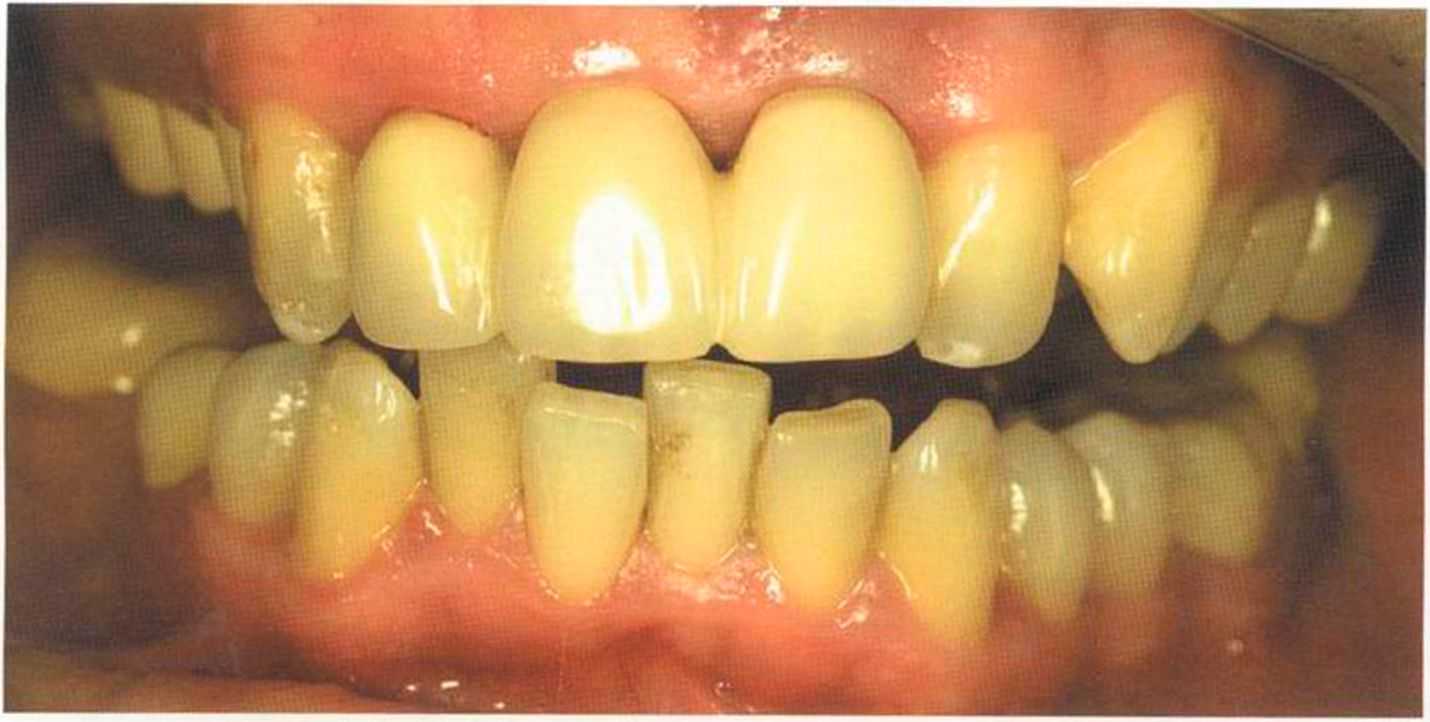

Этот пациент — португалец. Он всю жизнь имел такое положение зубов. Небнорасположенный боковой резец теперь необходимо удалить, а затем воссоздать как эстетику, так и функцию в области фронтальной группы зубов. Планируется изготовить коронки In-Ceram в области 11 и 21 и соединить их вместе из-за увеличивающейся подвижности зубов.

Препарирование, проводимое доктором Риссе, оценивается как очень сложное. Режущие края центральных резцов сильно дивергируют, что создает неудобство при формировании хорошего уступа.

Из-за сильной протрузии центральных резцов на них всегда падает итого света, и они кажутся очень большими. Чтобы смягчить этот эффект, мы выбрали более темный цвет для реставрации.

Фото сверху и слева: отличный результат препарирования зубов с уже уложенными нитями для снятия оттиска.

Готовая работа привела в восторг нашего пациента. Он даже не мог себе представить, что соединенные вместе коронки могут выглядеть так естественно. Мы решили не копировать на реставрацию белое пятно, имеющееся на 12 зубе.